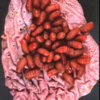

Q

What lesion is shown here?

A